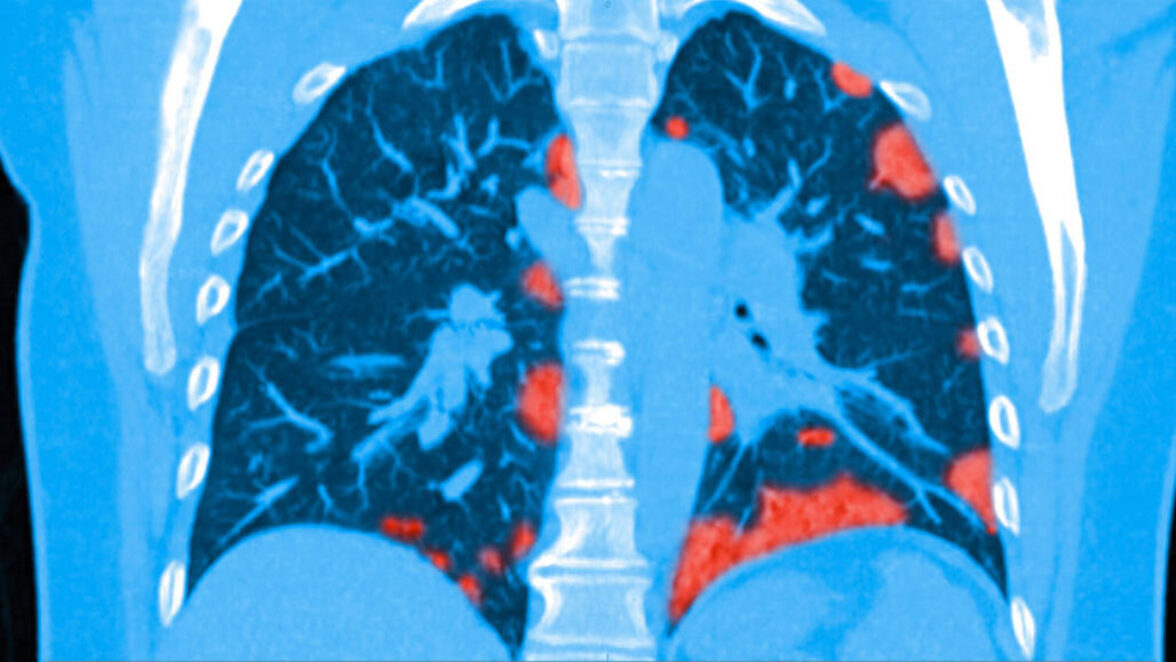

В тяжелых случаях КОВИД-19 может распространиться за пределы легких и на другие органы, такие как сердце, печень, почки и части неврологической системы.